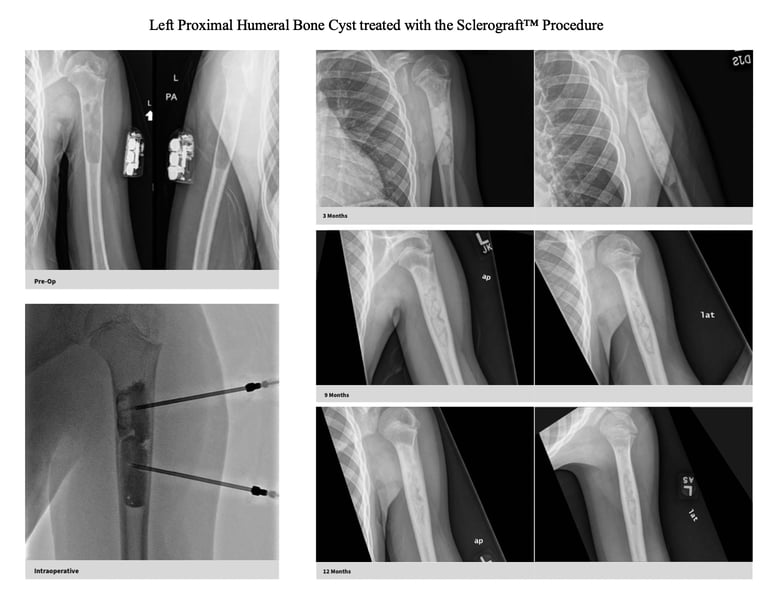

Gallery

Explore our educational resources and images